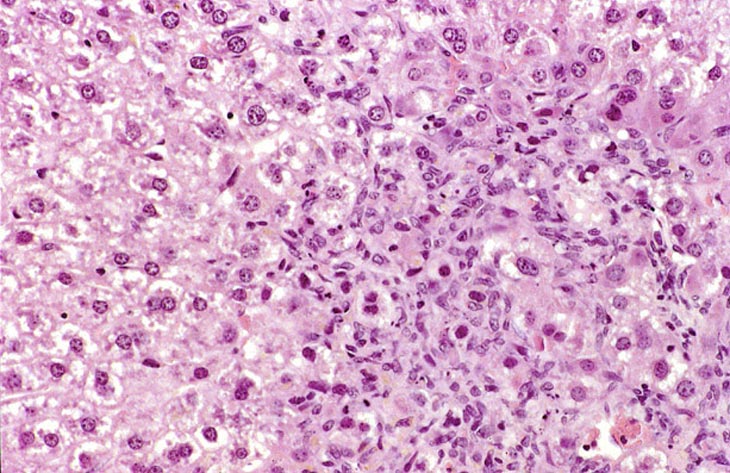

This change was originally diagnosed as endothelial cell proliferation. Based on the H&E stained sections, it is not possible to definitively identify the proliferating sinusoidal lining cells as endothelial cells but some have cytomorphological features consistent with endothelial cells. Low and high magnifications of endothelial cell hyperplasia.